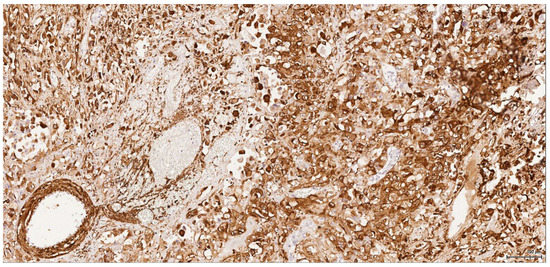

Immunohistochemical profiles (Table 1) point towards a renal cell origin in some cases, thus excluding a urothelial nature for these tumours. All six tumours are vimentin-positive (Figure 4); in three cases (1–3) the epithelioid component is coexpressing CD10 (Figure 5) and is negative for CK7 (Figure 6), CK20, p63 and CKHMW. This profile strongly favours renal cell origin.

Figure 4. Vimentin: Male (case 2): intense and diffuse reaction.